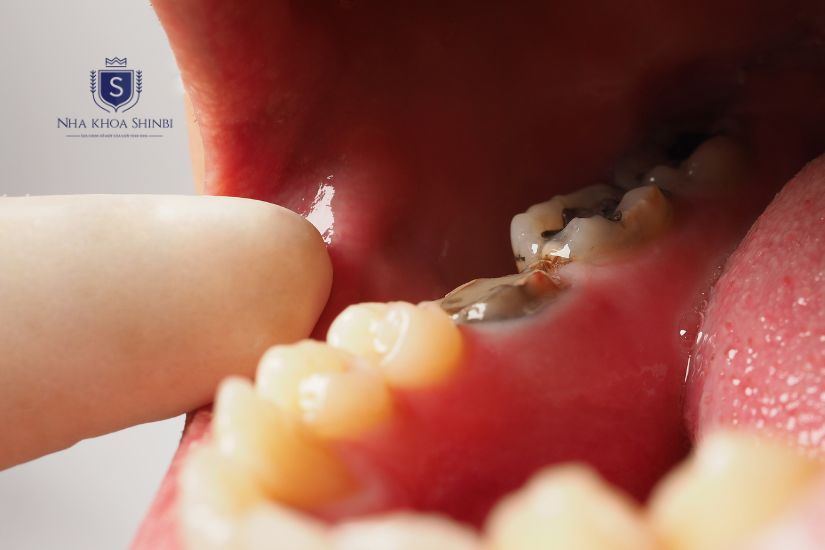

Răng cấm bị sâu nhiều

Răng cấm bị sâu

- Răng bị sâu nặng, không thể phục hồi bằng phương pháp trám hoặc bọc răng sứ.